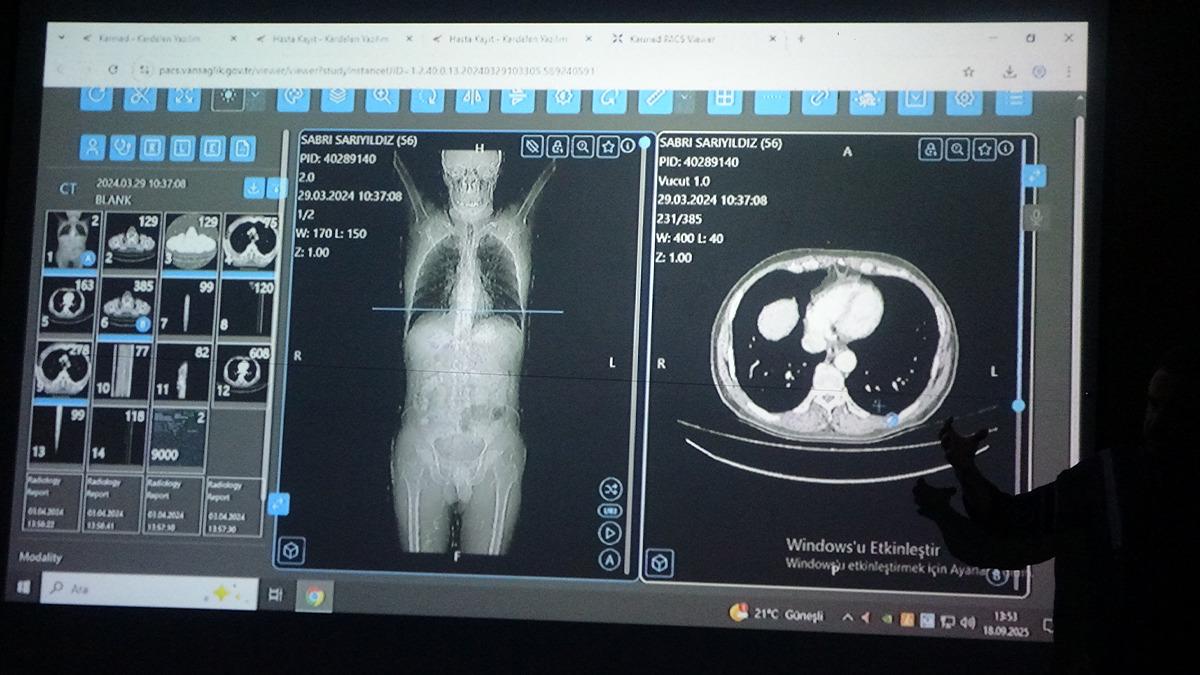

Çalışmada örnek vakalardan biri olarak, Erciş ilçesinde yaşayan 56 yaşındaki Sabri Sarıyıldız değerlendirildi. Yapay zekâ destekli yazılımın önerdiği tedavi planı, hekimlerin kararlarıyla birlikte uygulamaya konuldu. Sarıyıldız, izlenen bu yol sayesinde gerçekleştirilen başarılı cerrahi operasyon sonrası sağlığına kavuştu.

Konuya ilişkin konuşan Van Bölge Eğitim ve Araştırma Hastanesi Genel Cerrahi Uzmanı Prof. Dr. Sebahattin Çelik, yapay zekânın hekim kararlarıyla yüzde 76 oranında örtüştüğünü belirtti. Yapay zekânın sağlık alanında giderek daha yaygın kullanıldığı ifade eden Prof. Dr. Çelik, "Biz de Van Bölge Eğitim ve Araştırma Hastanesi olarak teknolojinin sunduğu en son imkânlardan faydalanarak hastalarımıza doğru tedaviyi ve doğru yaklaşımı sunmak için yapay zekâ algoritmalarını kullanıyoruz. Yakın zamanda prestijli bir dergide yayımlanan çalışmamızda, multidisipliner tümör konseylerinde yapay zekâ destekli bir yazılım kullandık. Bu konseylerde genel cerrahi, onkoloji, radyoloji, nükleer tıp, radyasyon onkolojisi ve patoloji gibi birçok farklı branştan uzman hekimler bir araya gelerek hastaların tedavi sürecine yönelik ortak kararlar almaktadır. Biz de bu konsey toplantılarında yapay zekâyı bir katılımcı olarak değerlendirdik. ChatGPT'nin son algoritmasını kullanarak kanser tanısı olan 100 hastamızı hem uzman hekimler hem de yapay zekâ değerlendirdi. Sonrasında alınan kararlar karşılaştırıldığında, yapay zekâ destekli verilen kararların hekimlerin kararlarıyla yaklaşık yüzde 76 oranında örtüştüğünü gördük. Bu oldukça çarpıcı ve önemli bir bulgudur. Çünkü bu durum, yapay zekâ algoritmalarının artık profesyonel bir meslek grubu olan doktorlara yakın düzeyde karar verebildiğini göstermektedir" dedi.